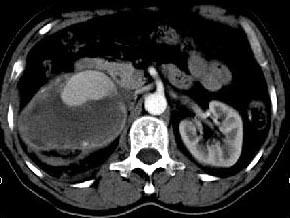

问题 男,48岁,反复腰酸、腰痛伴镜下血尿2年,加重3天,无尿频、尿急、尿痛,无低热、盗汗、咳嗽,右肾区叩击痛,CT检查如图所示,应诊断为 ( )

选项 A、右肾错构瘤 B、右肾盂癌 C、右肾癌 D、急性右肾内血肿 E、右肾动脉瘤

答案 E